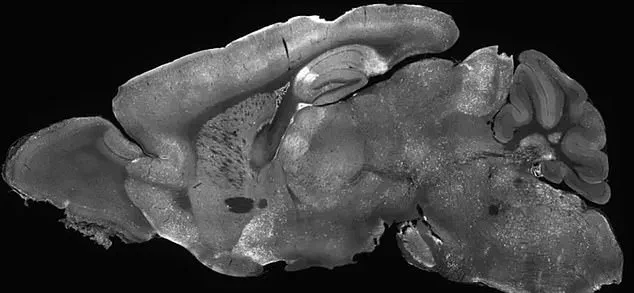

The therapy involved injecting the modified adenoviruses into the mice's cerebral ventricles, the fluid-filled cavities in the brain, using a needle inserted past the eye.

This technique, though invasive, demonstrated the feasibility of targeting specific brain regions with precision.